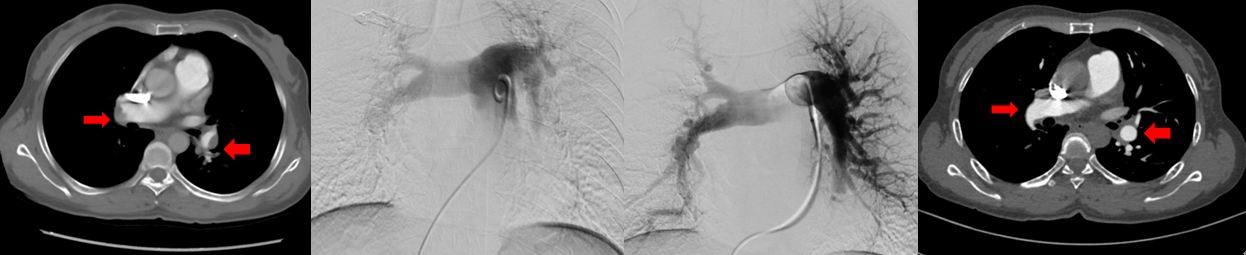

术前双侧肺动脉主干内血栓,术中溶栓后改善,术后复查主干血栓消失

北京清华长庚医院血管外科团队在吴巍巍主任的带领下联合麻醉科心内科呼吸科重症医学科等兄弟科室充分评估患者病情明确患者手术指征制定详细的围手术期治疗预案,与患者及家属充分沟通手术的必要性及相关风险后决定采用肺动脉球囊扩张成形术治疗。这是血管外科在静脉血栓栓塞性疾病治疗中的又一次大胆的尝试,无论是医生或是患者均承担了相当大的风险及压力。219日在麻醉科的严密监测下吴巍巍主任、赵俊来医通过右侧股静脉入路选择进入患者左肺动脉基底段狭窄部位,完成肺动脉球囊成形术,球囊扩张后肺动脉形态改善患者术后在监护病房观察一天后顺利返回普通病房,患者恢复顺利。于225再次行右侧肺动脉基底段球囊扩张。患者术后6分钟步行距离明显提高,术后2天即可行走450m,肺动脉力由术前82mmHg降至68mmHg患者顺利出院,由于双侧肺动脉病变广泛,此后还将密切随诊,择期再次行其余部位的肺动脉腔内治疗。

双侧肺动脉基地段狭窄球囊扩张前后对比